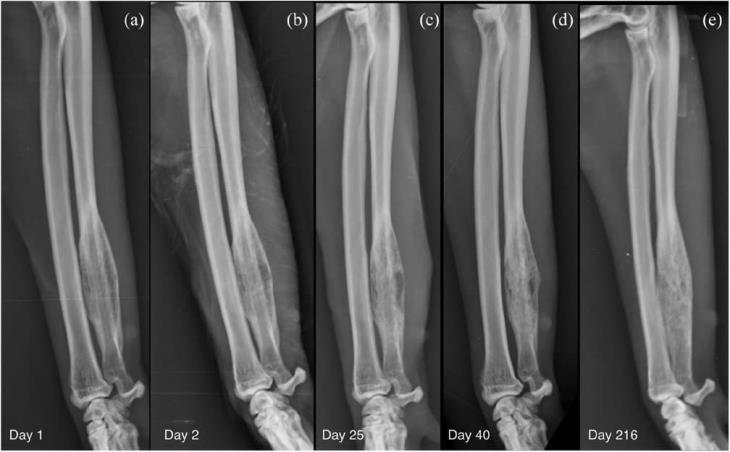

Multiple bone biopsies were performed using a 14 G Jamshidi needle (T-Lok; Argo). Two samples were taken from the centre and two from the periphery of the lesion. Post-biopsy radiographs of the right antebrachium showed no evidence of iatrogenic fractures. Based on the presumption of a bacterial disease process, a 2-week course of amoxicillin–clavulanate (Clavamax; Beecham) 20 mg/kg PO q12h was started along with a 7-day course of meloxicam (Metacam; Boehringer) 0.1 mg/kg PO q24h. Subsequent histological diagnosis was consistent with multifocal, marked, neutrophilic and lymphocytic osteomyelitis. Microbiology was negative for aerobic and anaerobic culture, fungal culture and mycobacteria. Furthermore, fluorescence in situ hybridisation (FISH) analysis did not detect any bacteria. No further antibiotics were prescribed. Following the initial presentation (Figure 4a), radiographic follow-up was performed at day 25 (Figure 4b) and day 40 (Figure 4c) from diagnosis (5 and 20 days after the end of the course of antibiotics). An increase in radiopacity of the lytic lesion was evident due to in-filling with bone on day 40 (Figure 4d). A further increase in radiopacity was noticed at a long-term radiographic follow-up performed at day 216 (Figure 4e). At this time clinical signs had resolved, with the absence of lameness and pain on palpation of the right forelimb.

Figure 4 Sequential mediolateral radiographs of the right antebrachium performed at (a) day 1 (day of presentation), (b) day 2 (after bone biopsy), (c) day 25 (5 days after the end of the initial course of antibiotics), (d) day 40 (20 days after the end of the initial course of antibiotics), (e) day 216 (long-term follow-up). The radiograph performed after the bone biopsy (b) shows a defined area of radiolucency in the centre of the lesion representing the bone deficit at the biopsy site. An increasing opacity within the lesion with a less moth-eaten appearance of the medulla, smoothing of the caudal and cranial bony contours and merging of the periosteal new bone with the cortex on follow-up radiography represents bone production as healing takes place (c–e); however, bone remodelling at the long-term follow-up was slower than expected.